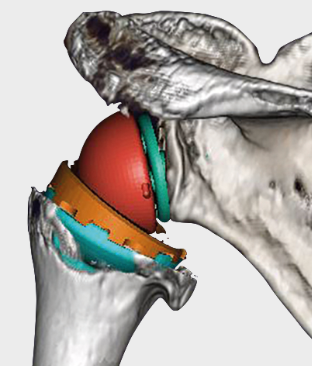

어깨 치환술(Total Shoulder Arthroplasty)

적응증: 이 수술은 심각한 어깨 관절염, 회전근개 파열, 기타 어깨 관절 문제가 있는 환자에게 권장됩니다.

절차: 어깨 전치환술에서는 어깨 관절의 볼(상완골두)과 소켓(관절와)을 모두 금속과 플라스틱으로 만든 인공 부품으로 교체합니다.

혜택: 어깨 치환 수술은 만성 어깨 통증을 완화하고, 어깨 이동성을 향상시키며, 환자의 머리 위 활동 수행 능력을 향상시킬 수 있습니다.